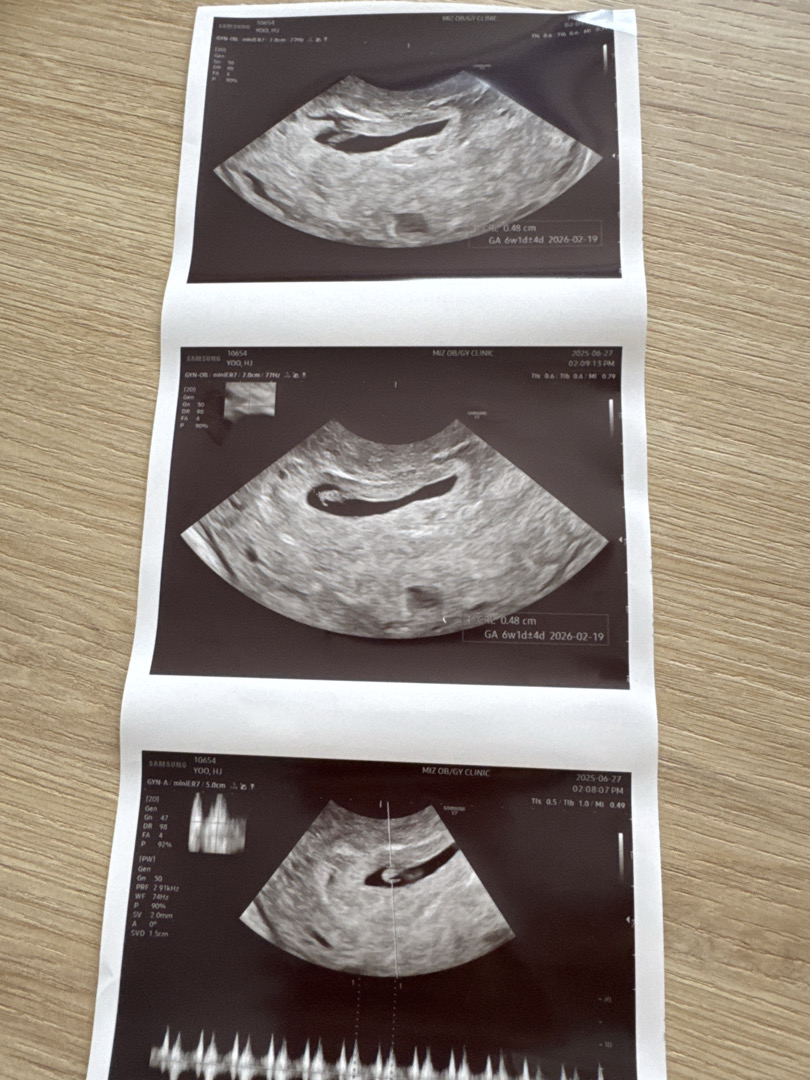

난황 위치

아들 원하는데 난황 왼쪽에 있으면 아들인가요? 각도에 따라서 틀리다 하길래 의사선생님한테도 여쭤봤는데 왼쪽으로 치우쳐 있다고 하네요